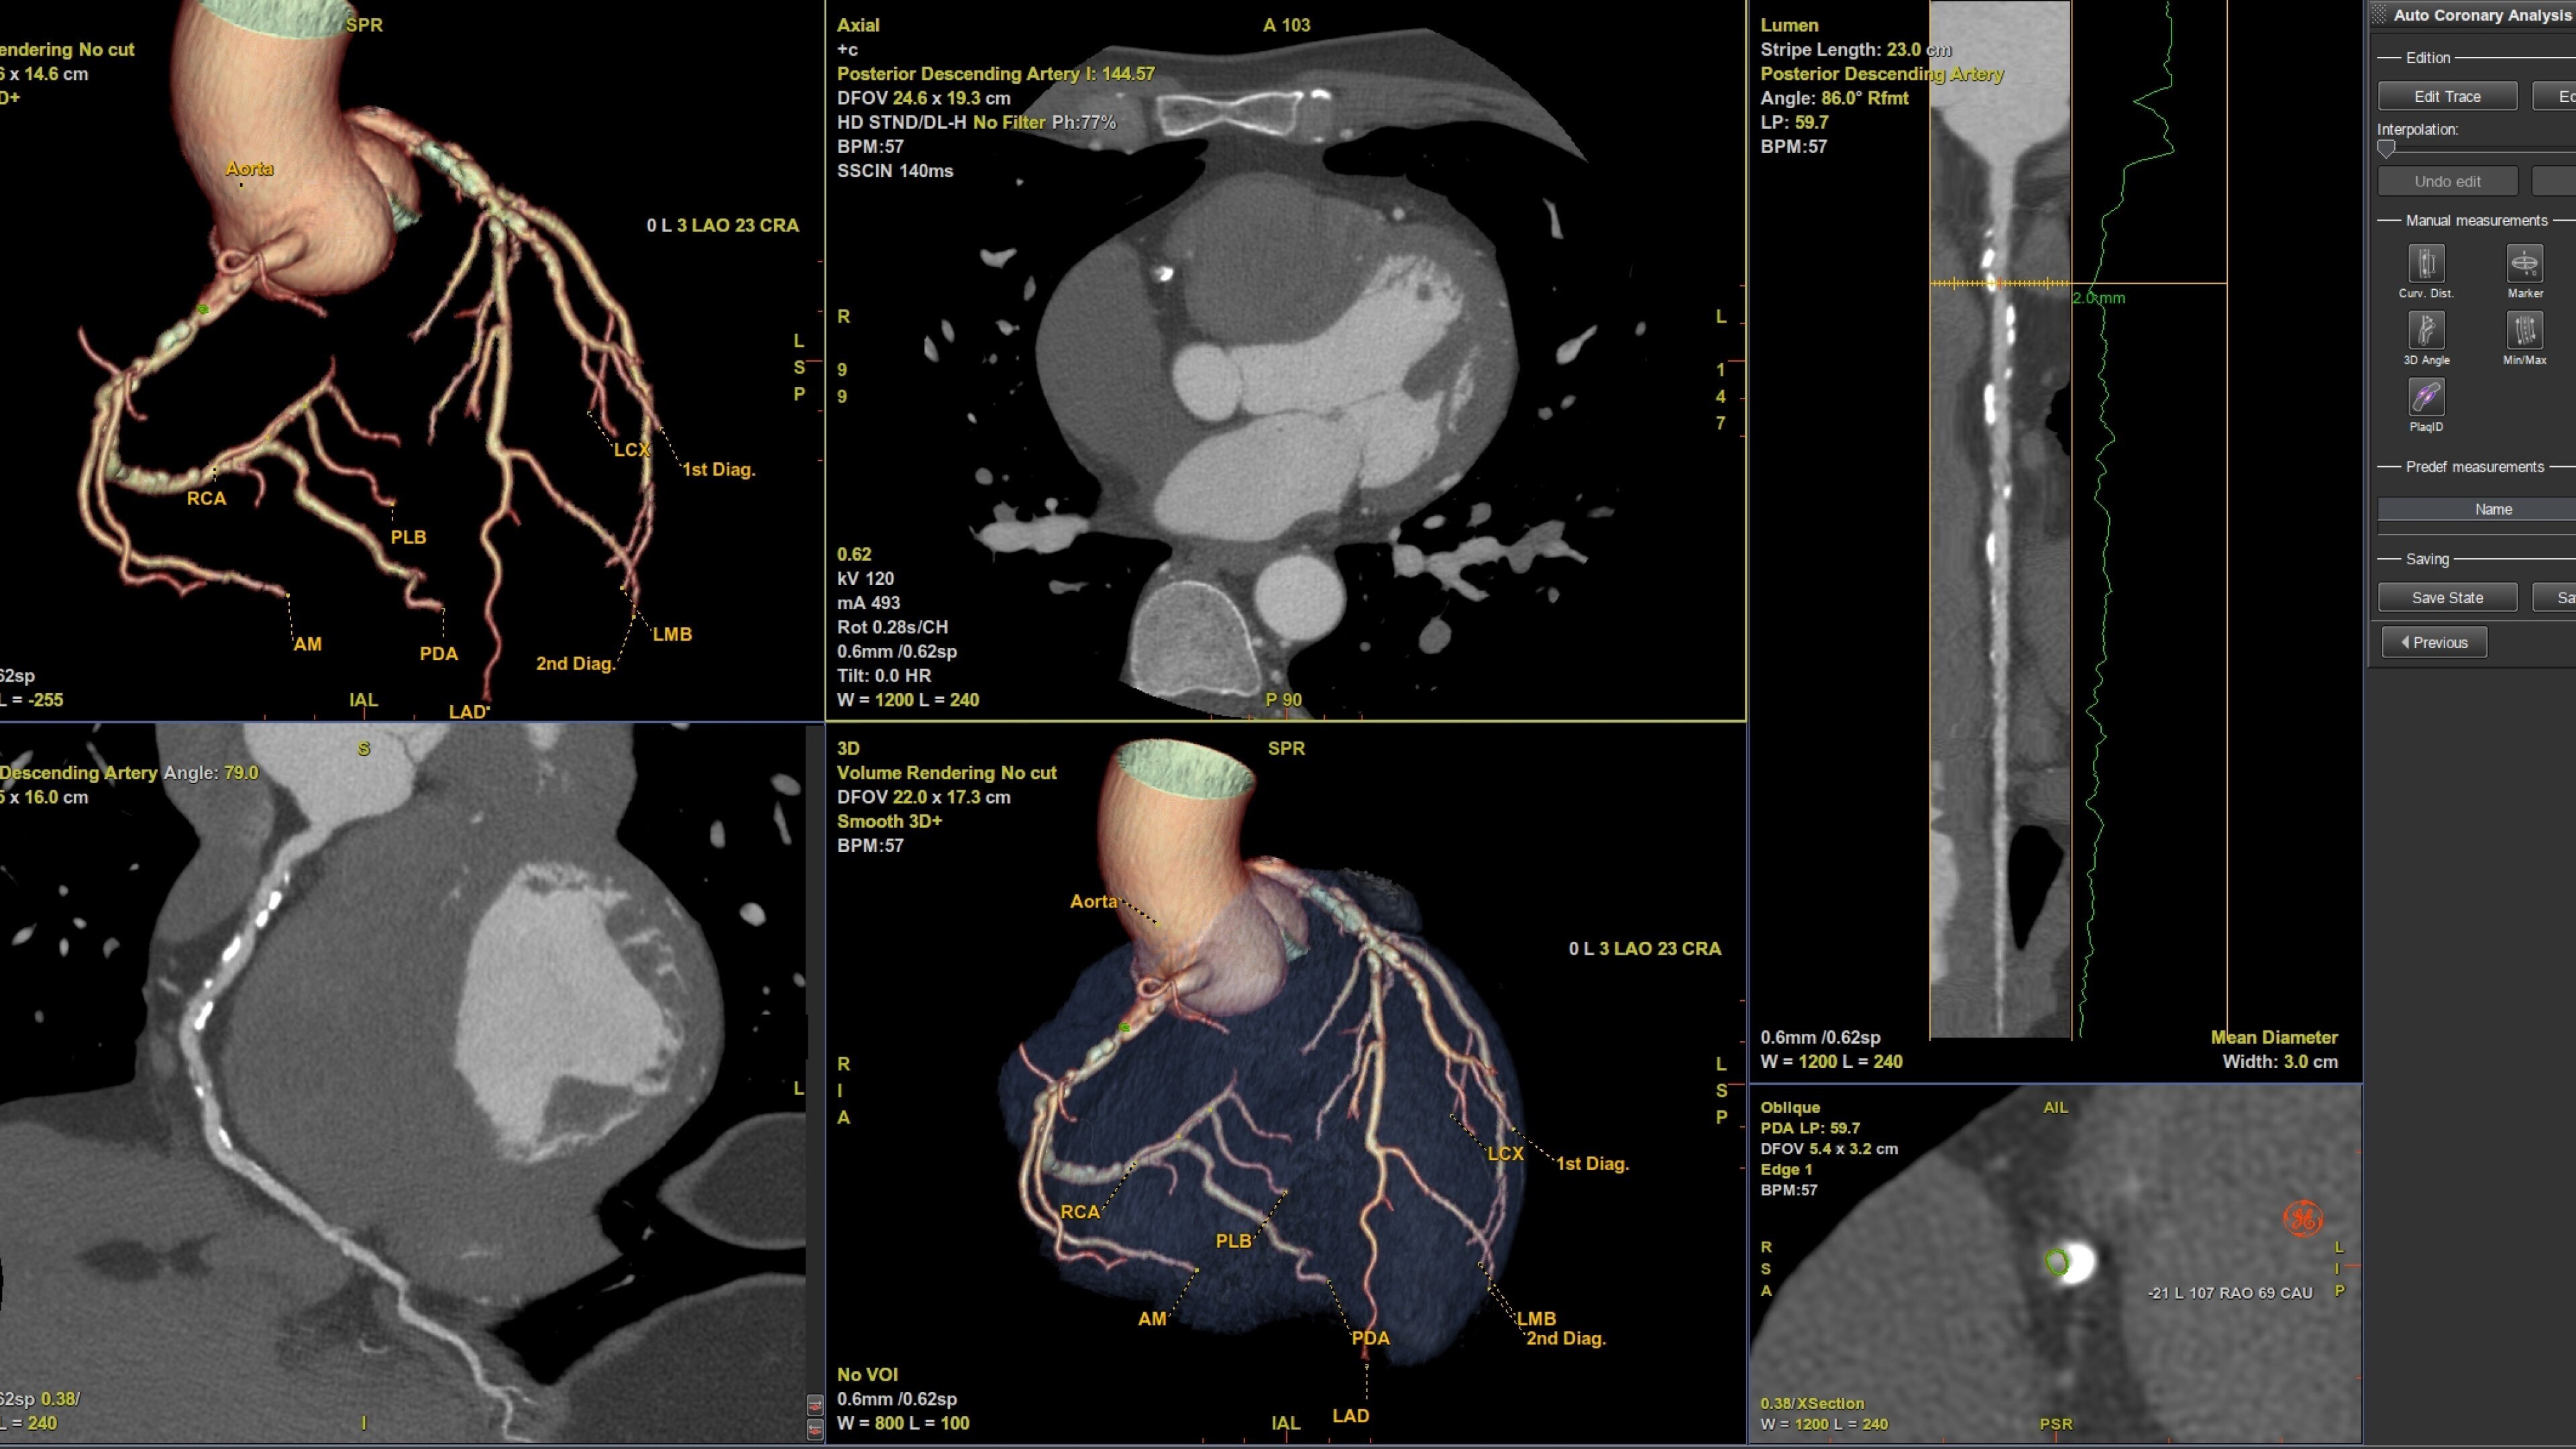

Automatically segments the coronary tree, tracks and labels the coronary arteries

• Auto Coronary analysis automatically segments the coronary tree, tracks and labels the coronary arteries

• Three pre-defined orientation protocols for easy review of the coronary vessels and chambers

• Plaque ID provides volume measurements for four distinct Hounsfield ranges to aid with identification and visualization of coronary plaque